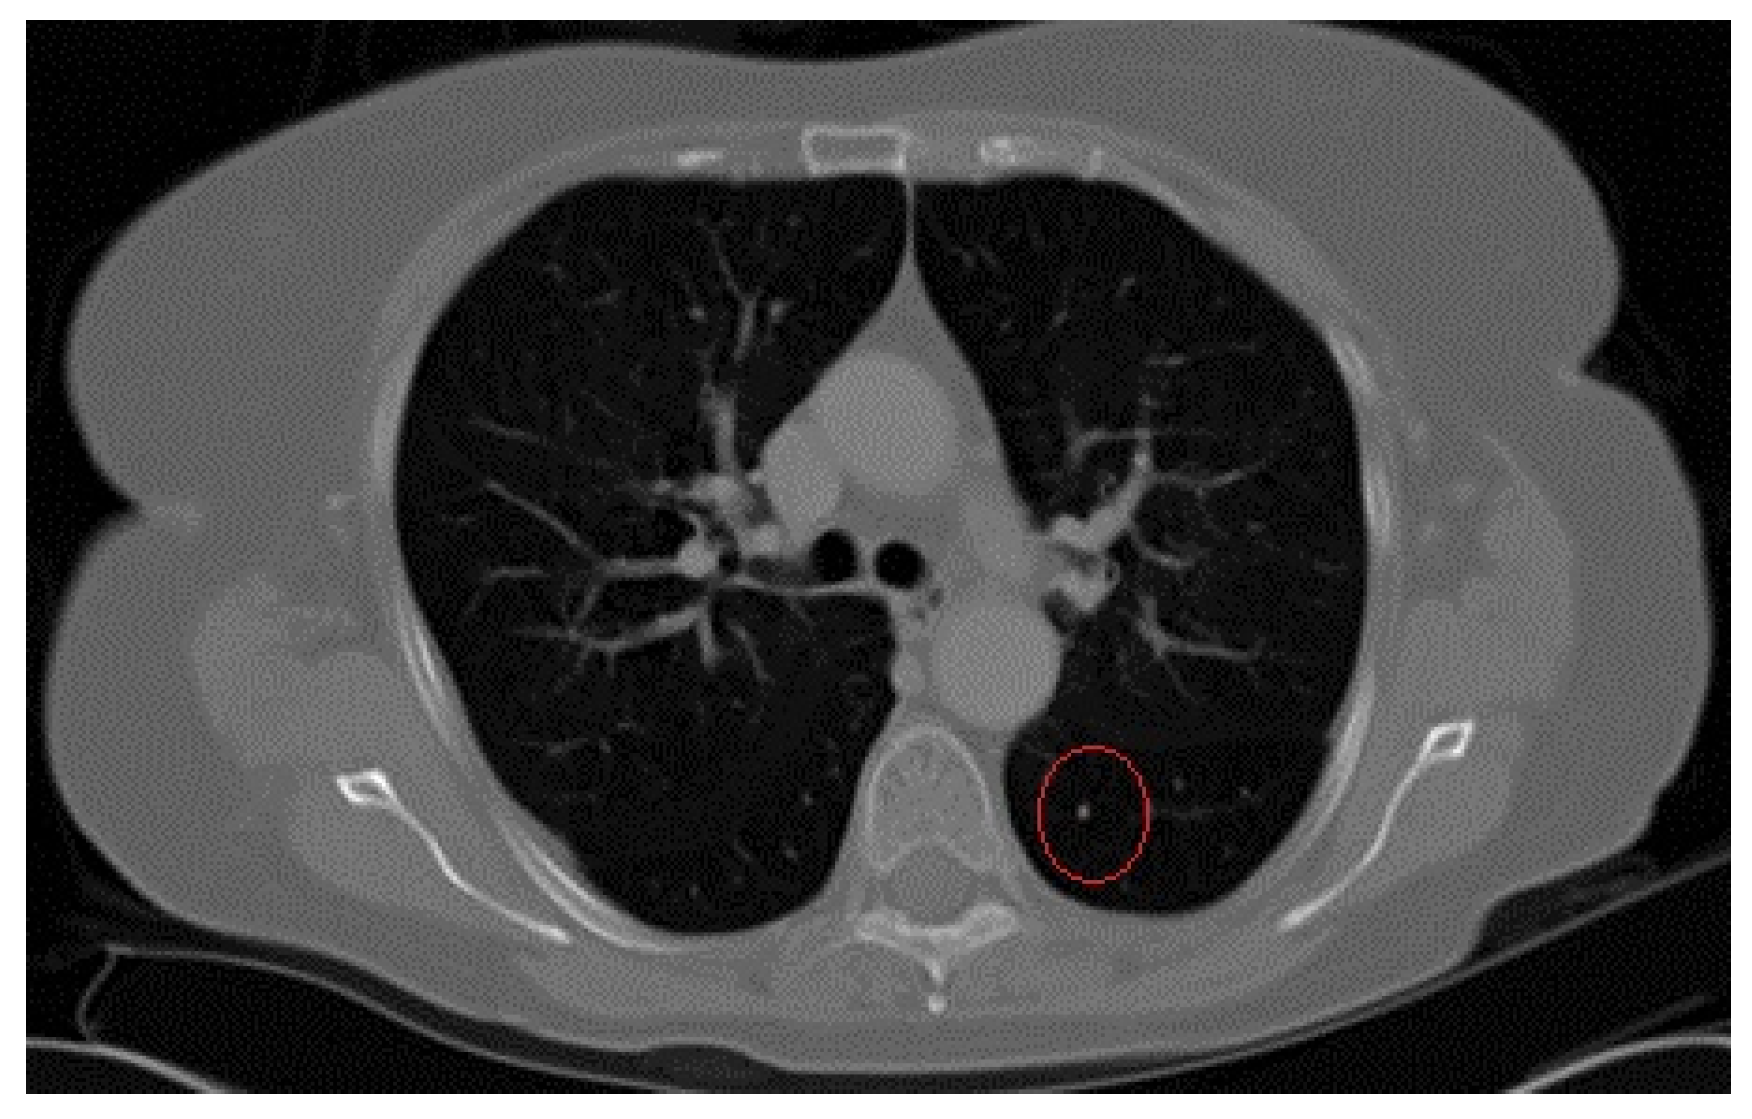

The initial dataset had 95 patients, where each patient had gone through one CT scanning process. One such process produced 64 CT images (slices) of the chest of the patient. This means that the initial dataset had 6080 images that the DNN used for training and testing. One of the 64 slices (images) is shown on Figure 1. Next, these images were labeled by medical personnel as cancerous or cancer-free and the initial dataset was divided into the two piles. In our case, we had 73 patients who were diagnosed the possibility of cancer (Pile 1) and 22 who were without cancer (Pile 2).

Figure 1.

A cancerous Computed Tomography (CT) image predetermined by medical personnel and confirmed by using biopsy of the tissue.